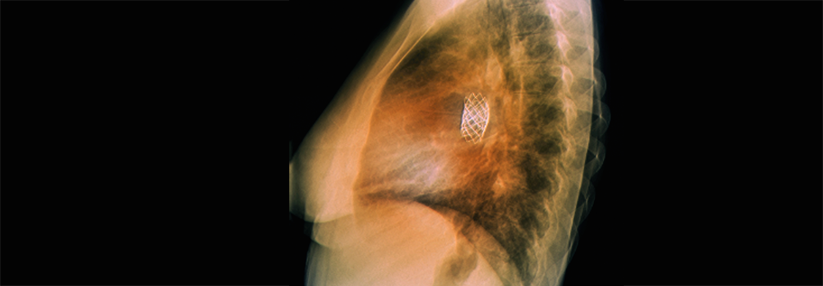

Ohne Frage stellt ein angeborener Herzfehler bei einer Schwangeren ein Risiko dar, sowohl für die Frau als auch für das Kind. Insgesamt liegt die Komplikationsrate aber eher niedrig.

Dank des medizinischen Fortschritts können sich heute viele Frauen mit angeborenem Herzvitium ihren Kinderwunsch erfüllen. Allerdings ist die Komplikationsrate für Mutter und Kind nach wie vor erhöht, wie eine Analyse von Versichertendaten ergab. Berücksichtigt wurden sämtliche 7.512 Schwangerschaften der Jahre 2005 bis 2018 von Frauen mit kongenitalem Herzfehler.